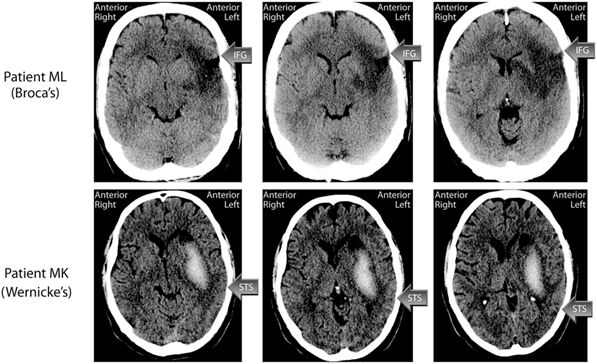

Wernicke aphasia←病灶在temperol lobe

Wernicke區受損

- 主要負責語言的理解,因此當這一區發生問題時,一般會叫感覺型失語症。

- 這型失語症的特色是聽都沒問題,講話也沒問題,然而由於對語言的理解出現狀況,因此往往會答非所問,甚至會自己創造新的詞語。

- 病人無法理解語言,甚至對於文字的閱讀跟書寫能力都會受到影響。